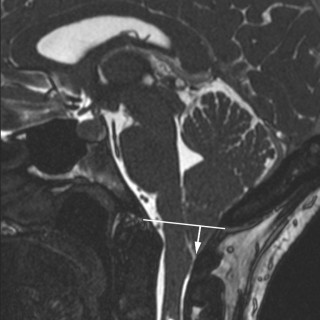

Eirik Helseth, Terje Rootwelt, Hanne Flinstad Harbo, red. Nevrologi og nevrokirurgi Fra barn til voksen. 7 utg. 582 s, tab, ill. Bergen: Fagbokforlaget, 2019. Pris NOK 899 ISBN 978-82-450-2473-9 Målgruppen för denna boken er som lärobok förstudenter och som uppslagsverk för hälsopersonal. Det är en väl inbunden bok med 39 kapitel som täcker de flesta medicinska aspekter på nervsystemets sjukdomar. Boken är rikligt illustrerad med teckningar av Kari Toverud, tabeller, foton och radiologiska bilder. Utvecklingen inom neurologi och neurokirurgi går snabbt och vi har fått uppleva flera...